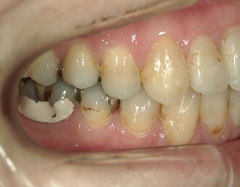

no.7_6967_治療前_右_01.jpgno.7_6967_治療後_正面_01.jpgno.7_6967_治療前_左_01.jpg

no.7_6967_治療後_右_01_640_480_やや高画質.jpgno.7_6967_治療後_正面_01.jpgno.7_6967_治療後_左_01.jpg